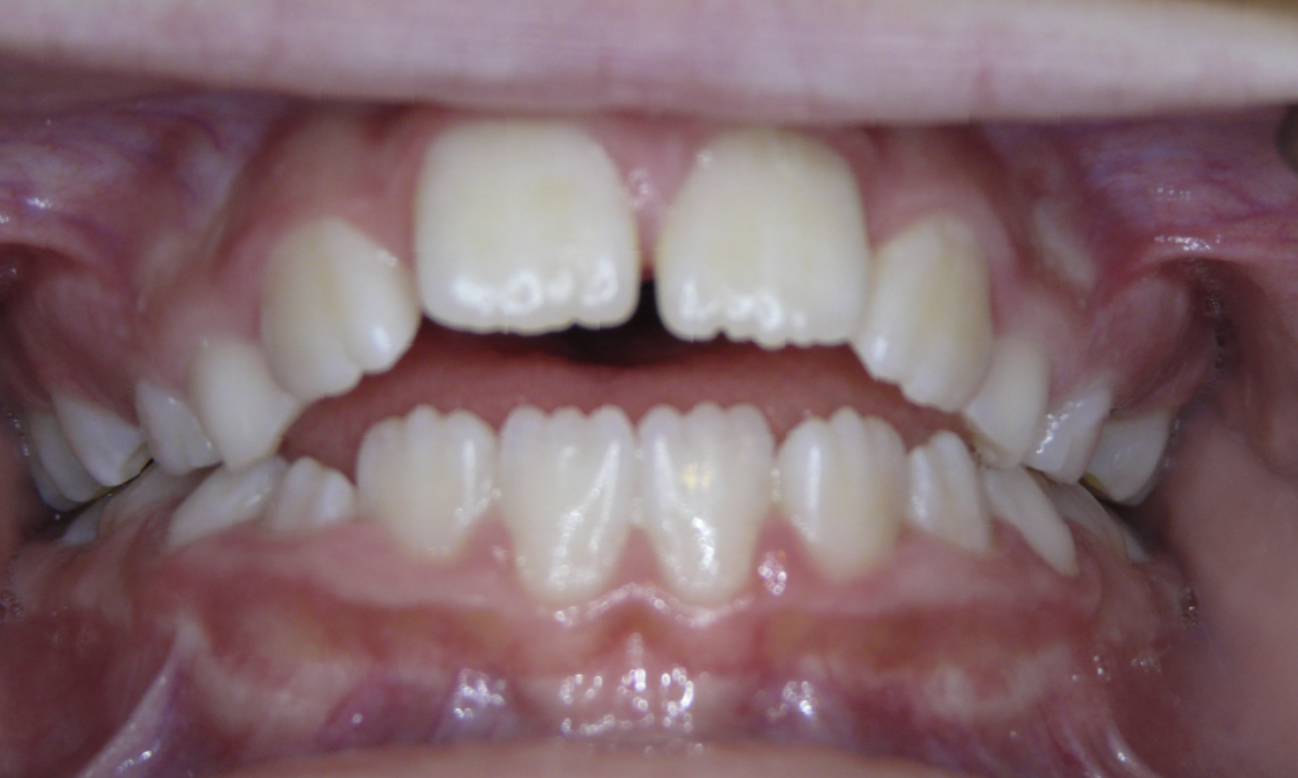

Diastema

Gaps between teeth